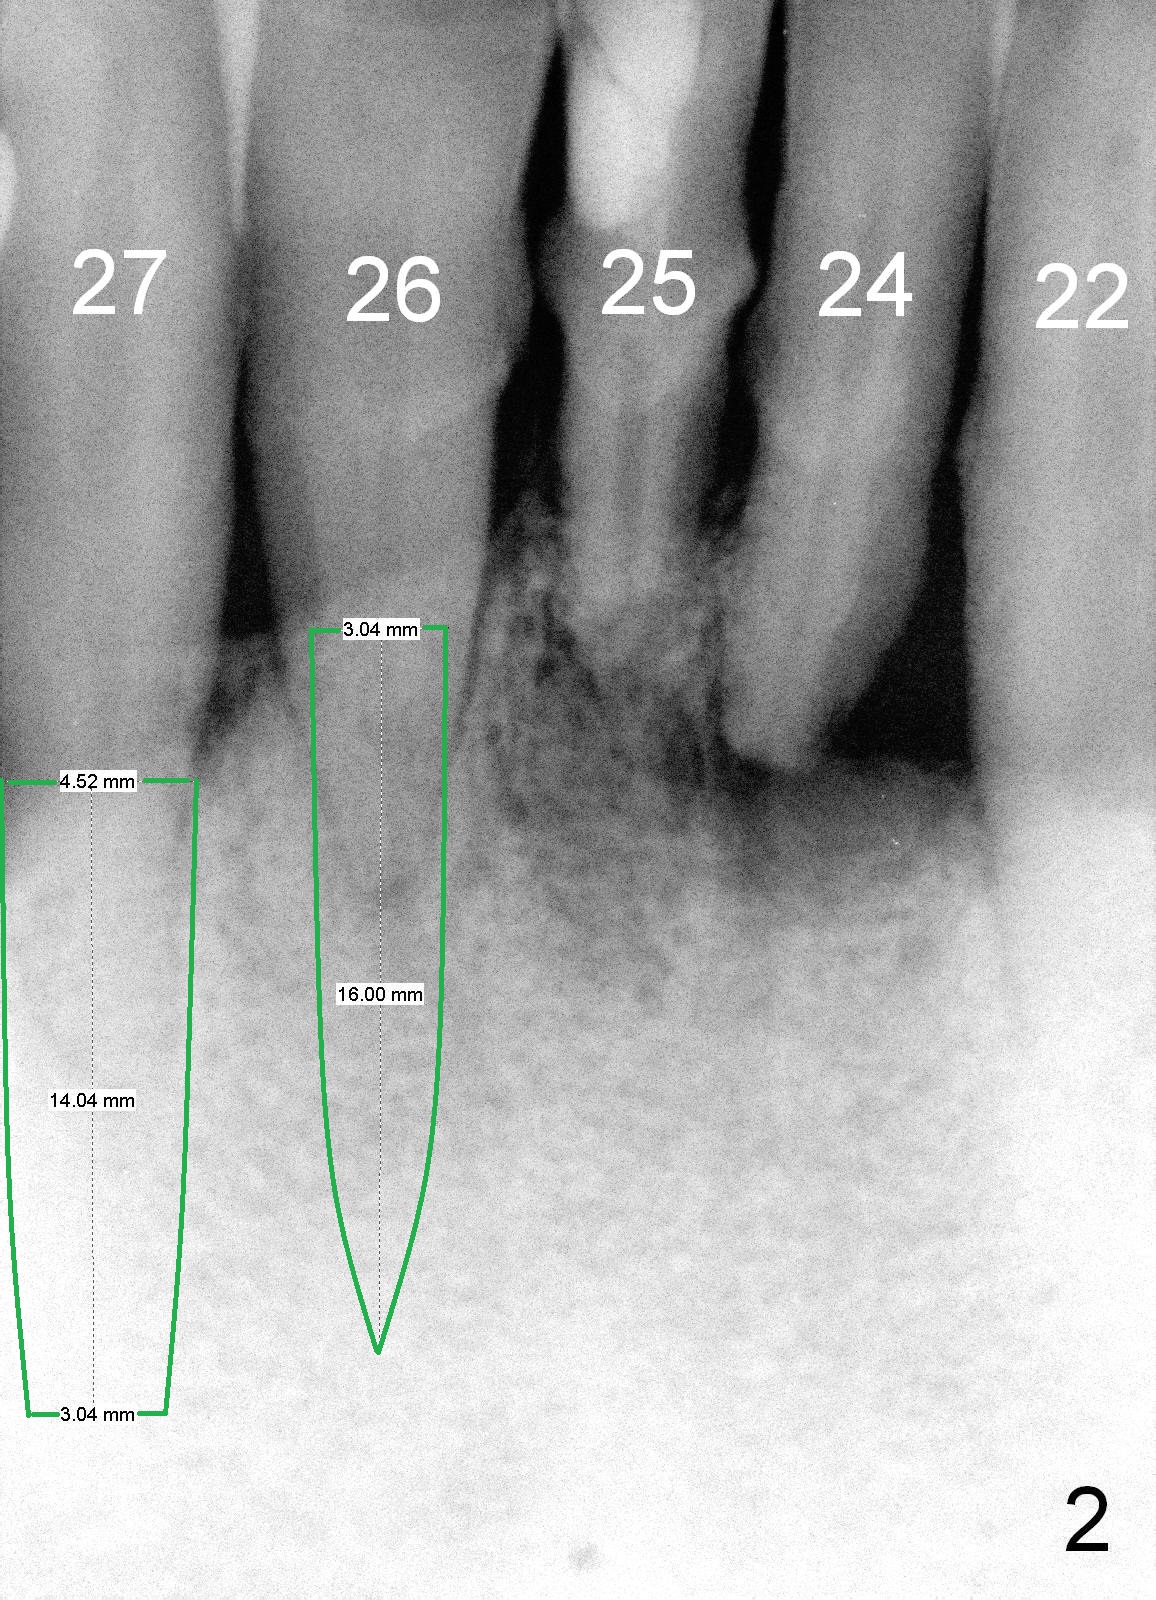

A 62-year-old man (CZ) has severe generalizd chronic periodontitis and occlusal trauma. Full mouth extraction and reconstruction is required. The patient prefers extraction by stage. The lower anterior segment reconstruction is our first treatment: from #22-28. The tooth #28 is exfoliated now (Fig.1 (full mouth X-ray was taken 4 years ago), 5). There are 3 incisors left. Two-piece implants are going to be placed for the canines and premolar, while 2 of 1 piece implants in the incisor sockets (treated with Metronidazole with Epinephrine gauze) for a bridge (Fig.2). Straight 1 piece 3 mm implants are routinely placed, whereas angled or 2.5 mm ones are backup. Two of 1.2 mm pilot drills and 3 of marked parallel pins may be needed.